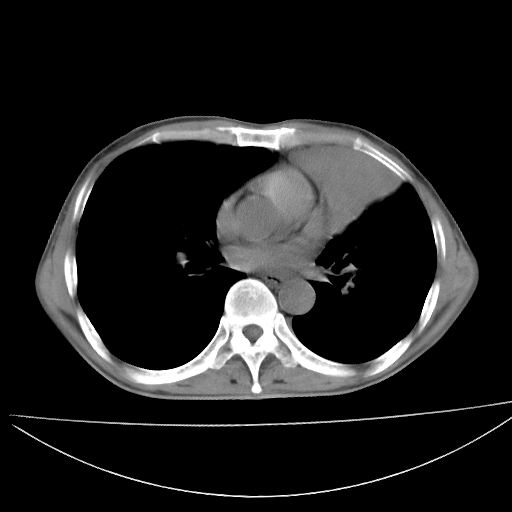

以下是引用杀毒软件在2009-4-28 17:58:00的发言:[br]考虑----左肺慢性肺脓肿形成继发上叶含气不良---抗炎后复查---待排肿瘤所致[br][br][本贴已被 杀毒软件 于 2009-4-28 18:01:26 修改过]